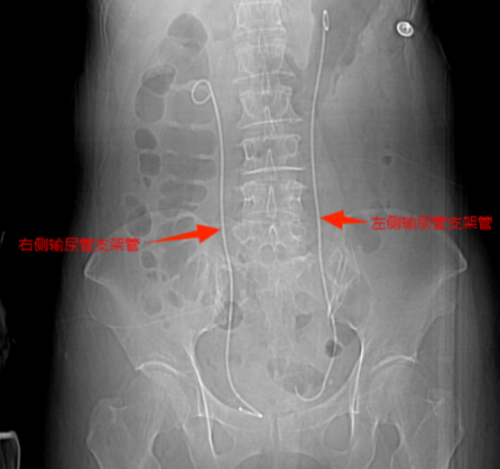

等到第二天送医时,张小华血压已降至78/42mmHg(血压<90/60mmHg称为休克血压),CT结果显示其双侧输尿管结石引发尿路梗阻,导致尿源性脓毒血症合并脓毒性休克。医院立即启动MDT多学科诊疗,泌尿外科一区主任傅发军带领团队紧急在急诊ICU实施床旁输尿管支架置入术,迅速解除梗阻,经抗感染等综合治疗,患者最终转危为安。目前,张小华已康复出院,择期再返院处理双侧输尿管结石。

双侧输尿管支架置入后解除尿路梗阻